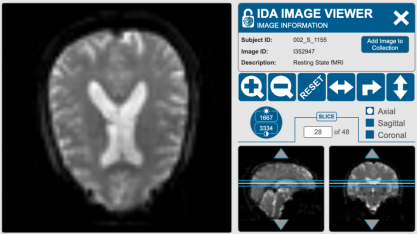

常见的功能性磁共振成像(fMRI)数据格式是DICOM(Digital Imaging and Communicationsin Medicine)。DICOM是医学影像领域的一种标准格式,用于存储医学影像数据,包括MRI、CT、PET等[7]。DICOM格式的fMRI数据通常包含多个序列,每个序列代表了一次扫描(即一个时间点),并包含了体积图像数据以及相关的元数据,比如扫描参数、患者信息等。这种格式在医学影像研究中广泛使用,并且可以方便地与其他医学影像工具和软件进行交互和分析。

图2 静息状态下不同位置人脑截面图[8]